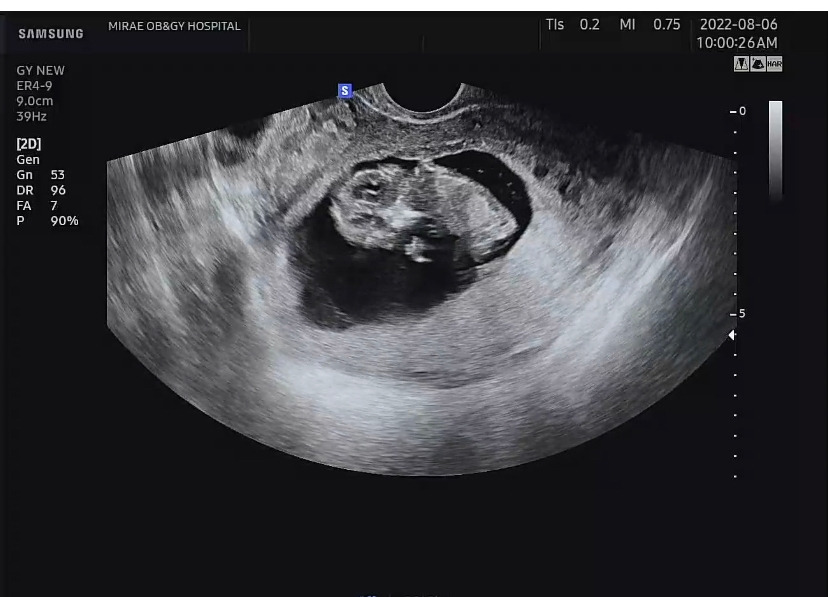

임신 11주차

아기크기 4.8cm, 심박수 165bpm

2주 만에 병원에 가니 아기는 2cm에서 4cm로 커있었다. 그리고 잔뜩 커버린 닭다리 모양이 되어 있었다. 그 사이 주수가 지나 이제 배 초음파를 볼 줄 알았는데 여전히 아래로 보는 초음파여서 조금 놀랐다. 오랜만에 본 아기는 발도 구르고 손도 좌우로 저어서 그 덕에 손가락과 손바닥 모두 구경했다. 달에 착륙한 우주인처럼 사뿐사뿐 폴짝폴짝 뛰기도 했다.

한 달 정도면 난임 병원 졸업이라 처음으로 일반병원에서 진료를 받았다. 난임 병원의 경우, 아기의 상태와 산모의 상태가 이성적으로 괜찮은지에 대한 빠른 확인과 내가 지켜야 할 것, 보충해야 할 영양, 조심해야 하는 것에 대한 끊임없는 조언과 처방이 전부였는데(사실 이 부분이 내가 가장 좋아하고 신뢰하는 부분이긴 했다), 일반병원에서의 진료는 사뭇 달랐다. 아기의 심박수를 10초 이내로 보던 난임 병원과 다르게 2배 이상의 시간을 들여 심박수를 봐주기도 하고, 초음파도 이리저리 돌려가며 꼼꼼히 봐주셨다.

11주차 초음파 사진 / 아기 양말